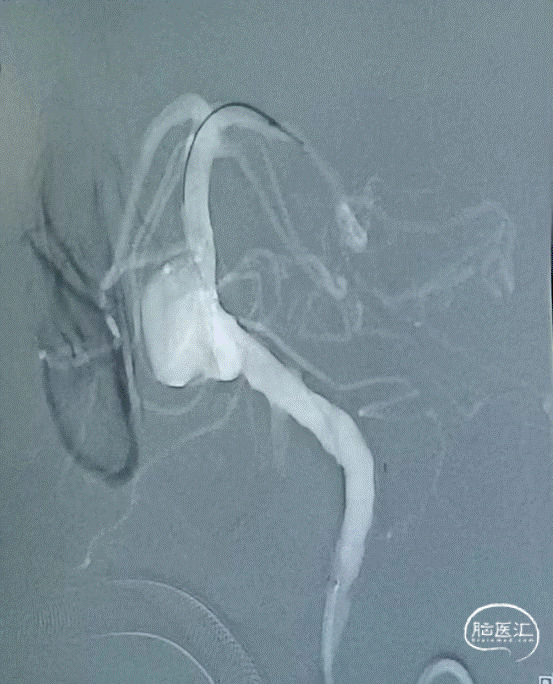

基底动脉局部呈瘤样扩张,瘤颈约13.66mm,最大截面大小约13.8mm*13.7mm,瘤内密度不均;左侧椎动脉V4多发钙斑附壁,相应管腔轻度狭窄;左侧颈内动脉虹吸部见钙斑附壁,相应管腔轻中度狭窄,最窄处位于C6,狭窄率约68%;左侧颈总动脉及颈内动脉C1近段见混斑附壁,相应管腔轻度狭窄,最窄处狭窄率约24%;主动脉见钙斑及混斑附壁,相应管腔轻度狭窄。

路图下支架微导管在微导丝引导下超选置于左侧大脑后动脉P2段,顺利建立通路,置入Nuva®血流导向密网支架。远端定位在动脉瘤中心以远25mm,近端定位在左侧椎动脉V4段拐弯处。